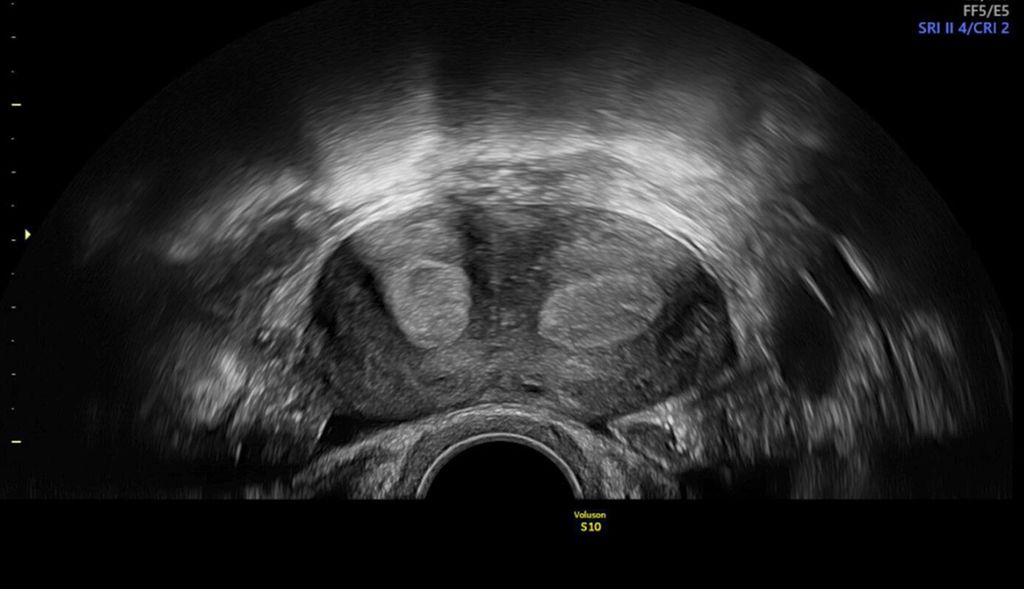

In unklaren Fällen, in denen die äussere Uteruskontur in der MPR nicht eindeutig zu sehen ist und so die Unterscheidung zwischen einem Uterus (sub-)septus und einem Uterus bicornis schwierig ist, hilft TUI bei der Differenzialdiagnose (Abb. 5 und 6).

Abb. 5: «Tomographic ultrasound imaging» (TUI). In mehreren parallelen Ebenen kann die äussere Uteruskontur analysiert werden (konvex vs. konkav)

Abb. 6: Uterus bicornis. Ist die äussere Uteruskontur in der MPR nicht eindeutig zu erkennen, hilft TUI (rechts)